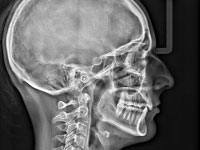

インビザライン治療に必要な検査(レントゲン・セファロ・CT・iPod撮影・iTero)を行います。

- セファロ撮影

- 矯正専用のレントゲン写真を撮影

- CT撮影

- 骨の状態や歯の位置などの確認できる歯科用CTを撮影